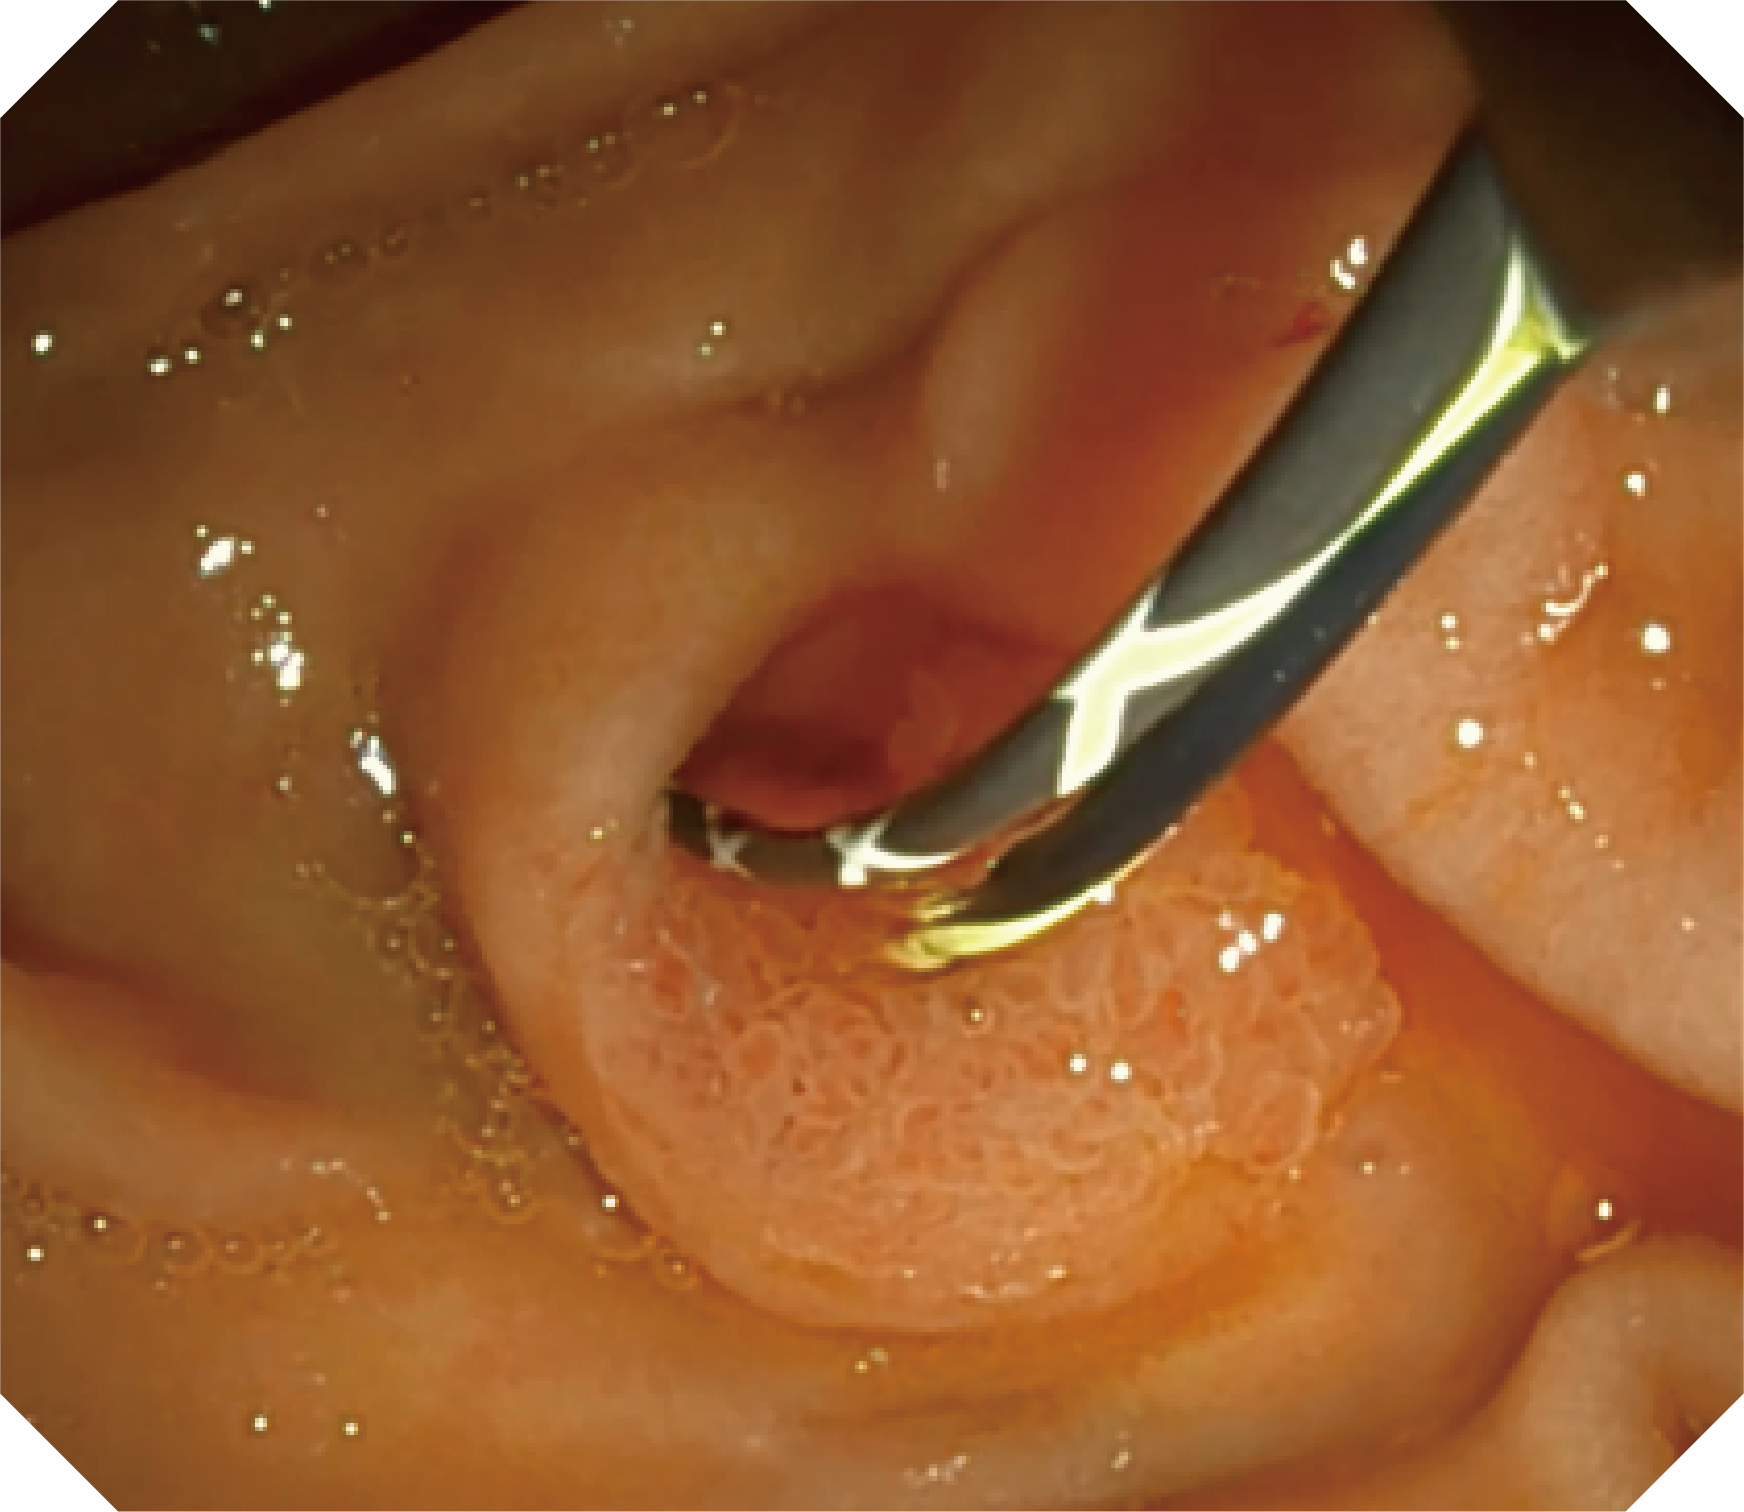

CMOS传感器提供高清内镜视野 SFI/VIST光学染色技术凸显病变区域

4.2mm大钳道,器械交换更顺畅

优异的手术器械抬举性

当切开刀伸出视野外时,导向面引导其回归视野